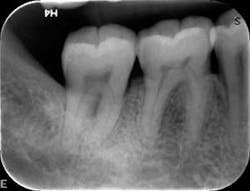

Dental examination revealed gingival swelling and bleeding on probing. Periodontal probing showed moderate-to-deep pocket depths in all posterior teeth (figures 1–3). Generalized bone loss was observed on radiographs (figures 4–6). Tooth vitality and percussion tests were negative. Teeth 2, 3, 31, 14, and 15 had Class III mobility. The patient was diagnosed with Type IV chronic adult periodontitis. Treatment options were discussed, and, after explanation, the patient agreed to the LANAP procedure.

Patient presentation before LANAP treatment (figures 1–6)